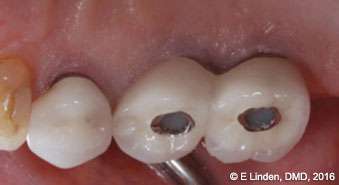

Follow-up examination: The patient returned for the first follow-up examination at 1 week postoperatively (Figures 10A-10C). The healing progressed well, and no signs of swelling or inflammation were present. During follow-up examination at 6 months postoperatively, the treatment site was completely healed with no signs of periimplantitis (Figures 11A-11C). The pocket depth, measured during the 6-month postoperative visit, was reduced to 3 mm-4 mm. (Significant improvement in comparison with the initial probing depths of up to 9 mm.)